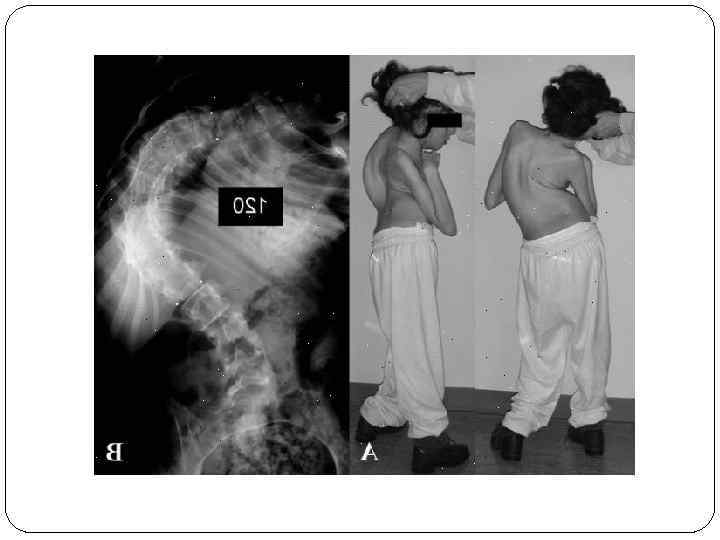

Дыхательные расстройства. Чаще всего встречаются такие дыхательные аномалии как нерегулярное дыхание, приступы гипервентиляции, апноэ продолжительностью иногда 1 -2 минуты, которых достаточно, чтобы вызвать цианоз и даже обморок. Дыхательные нарушения наблюдаются только в состоянии бодрствования. Сколиоз. Искривление позвоночника имеют минимум половина пациентов с синдромом Ретта. Сколиоз является следствием дистонии мышц спины и прогрессирует по мере развития заболевания.